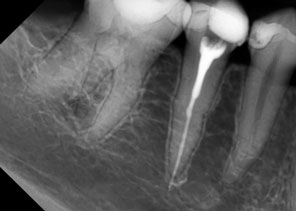

Качество снимков обладает высокой разрешающей способностью отношение сигнал /шум – важнейший фактор в получении изображения, составляет >37 dB, размер пикселя 0,035 мм. Благодаря высокой чувствительности и вариабельности размеров датчиков, визуализация становится детальной, в этой связи возможно проведение диагностики кариеса на контактных поверхностях. Преимущества данной методики при сравнении с пленочной рентгенографии состоит в скорости получения изображения объекта исследования, низкая доза облучения пациентов, возможность постпроцессорской обработки, визуализации деталей в диагностике послеоперационных результатов дентальной имплантации, эндодонтического лечения и постэндодонтического лечения (Рис.5), уточнения расположения кист, гранулем, конкрементов в протоках слюнных желез.

Рис. 5 Диагностика дентальной имплантации и эндодонтичского лечения.